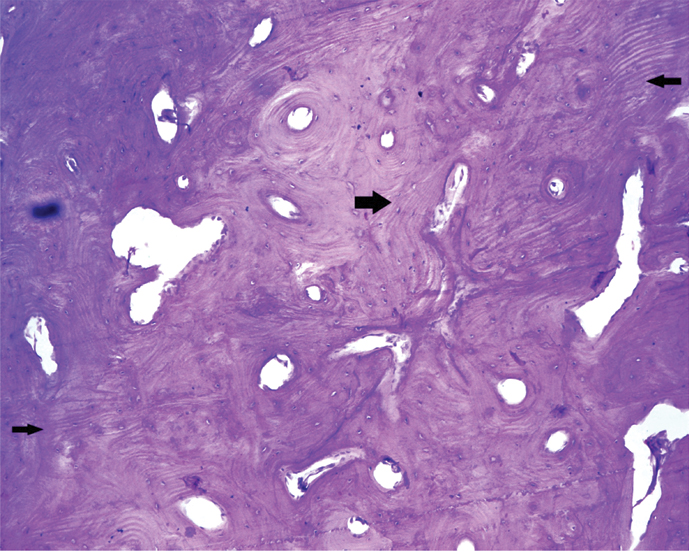

As patient was concerned about such large swelling over his face, plan of excision was made on the basis of cosmetic grounds. Patient was planned for excision with transcervical approach under general anaesthesia. A curvilinear incision was made from the chin midline, extending over the swelling, well below to preserve the marginal mandibular nerve and reaching till the mastoid tip. Subplatysmal flaps were elevated. A lobulated bony lesion was seen over the lower border of left mandible involving the buccal aspect extending medially to involve lingual aspect also [Table/Fig-3]. This bony tumour was cut from the mandible taking wide margin using oscillating saw with preservation of inferior alveolar nerve, alveolar rim and dentition. The mandible was reinforced using titanium plates [Table/Fig-4]. Histopathological examination showed mature lamellar bone consistent with compact osteoma [Table/Fig-5]. Patient did well in post-operative period.

Histopathology showing mature lamellar bony fragment. (H&E stain, 400X, black arrows).